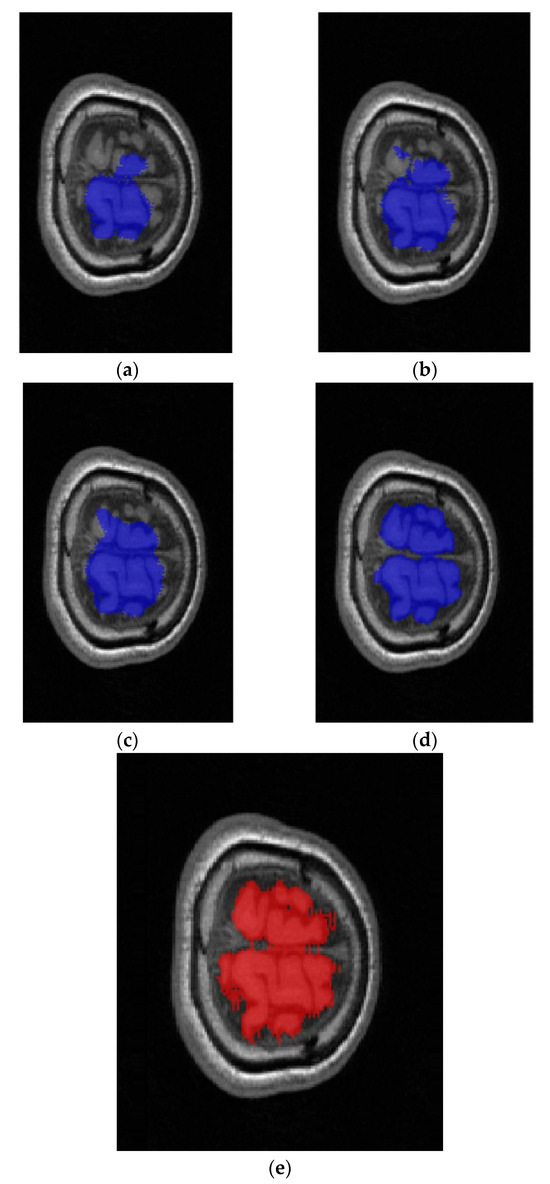

3.2. Results